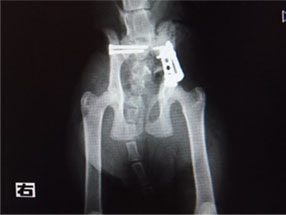

症例:交通事故による椎体脱臼

柴犬:9歳、避妊雌

交通事故直後、胸腰部に激しい疼痛、両後肢に完全麻痺を認め、シェフシェリントン徴候を呈していました。レントゲン検査において、第11-12胸椎間の脱臼が認められました。

脊髄の減圧、脊柱管の再構築・安定化を目的に、片側椎弓切除術およびMatrixMANDIBLE Plateによる椎体固定を実施しました。

隣接椎体を架橋するようにプレートを設置しました。

術後レントゲン写真